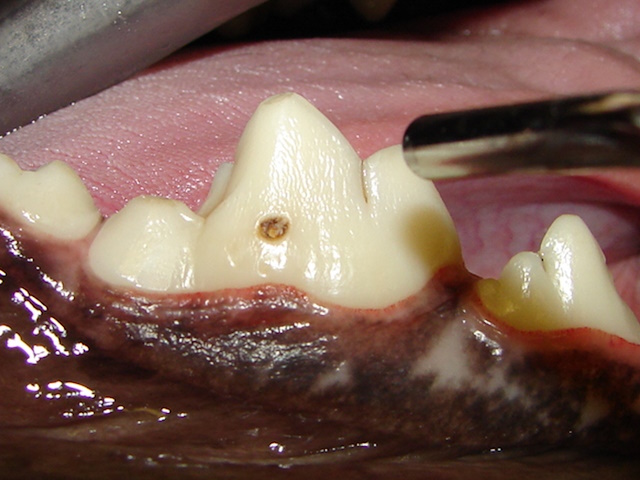

A small enamel defect is present on the outside surface of the lower first molar tooth in a dog.